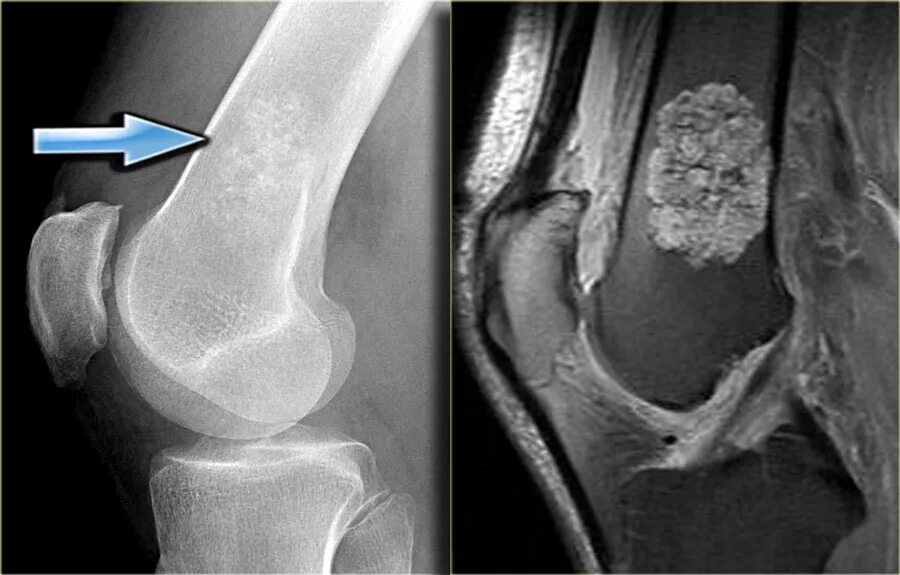

Экзостоз мкб 10